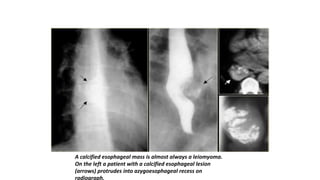

Leiomyomas

Leiomyomas are the most common benign esophageal

neoplasm and are often large yet nonobstructive.

A calcified esophageal mass is almost always a leiomyoma.

On the left a patient with a calcified esophageal lesion

(arrows) protrudes into azygoesophageal recess on

radiograph.